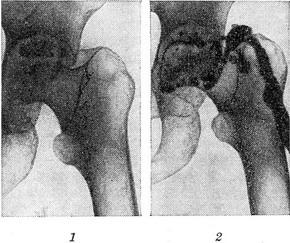

![]() Хронічний гнійний коксит, ускладнився некрозом частини головки стегнової кістки і утворенням свища: 1 - контрольна рентгенограма (до фістулографія); 2 - фистулограмма. |

Фістулографія - методика рентгенологічного дослідження норицевих ходів шляхом заповнення їх контрастним речовиною з подальшою рентгенографією (рис.). Основним завданням фістулографія є детальне вивчення характеру та напрямки норицевих ходів і їх розгалужень, а також встановлення наявності або відсутності зв'язку між свищуватими ходами і вогнищами деструкції (зокрема в кістках) та сторонніми тілами, секвестрами, абсцесами та іншими порожнинами, розташованими в сусідніх з свищевым ходом органах. Контрастне рентгенологічне дослідження порожнини абсцесу називається абсцессографией.